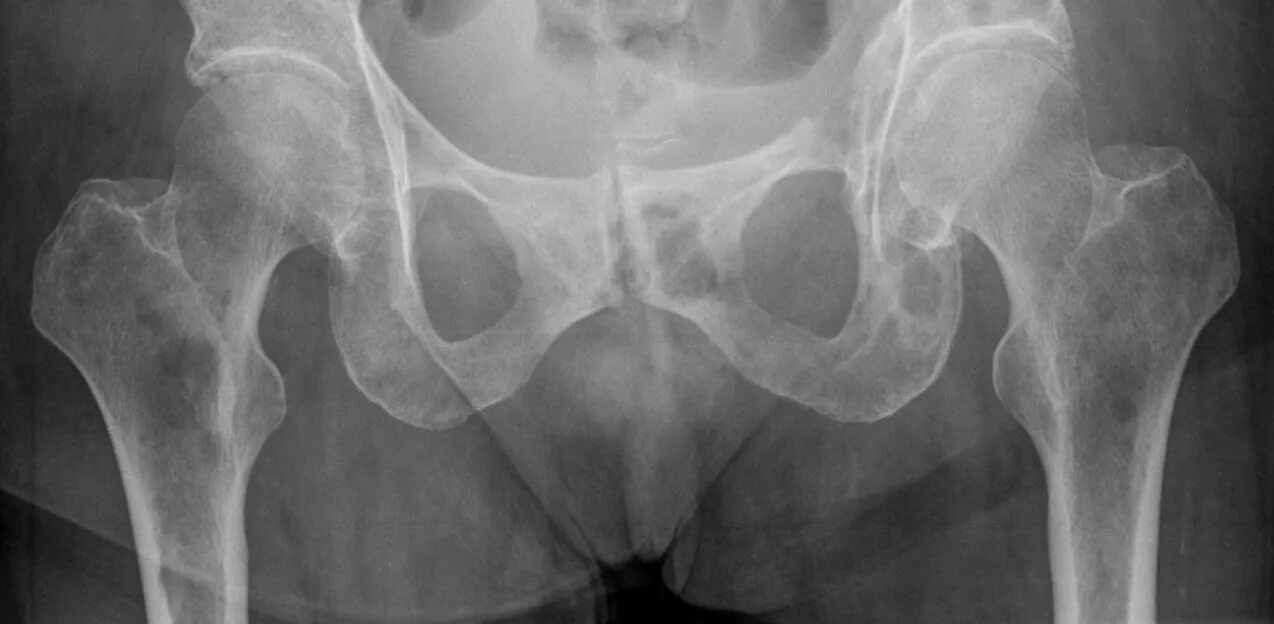

Метастазы в тазу